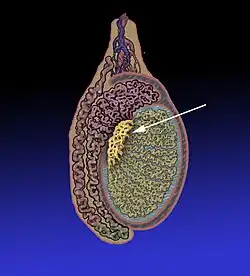

Position of the rete testis within the testicle | |